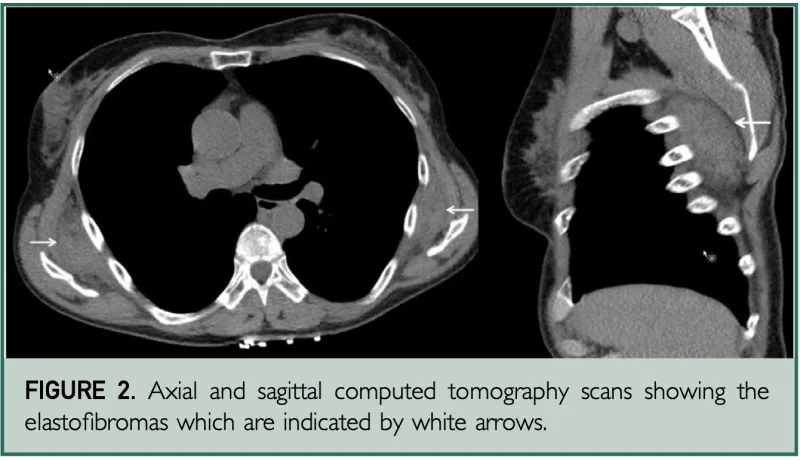

診断するためにCTを撮像することに.

肩甲骨の深部に胸壁から龍視する病変を認めます.

内部に脂肪が混入していて, 黒っぽいスジ状の陰影が入るのが特徴です.

引用元:Benson J. Bilateral elastofibroma dorsi mistaken for lipoma. Mayo Clin Proc. 2020. 95.

CTの結果, 内部に脂肪が混入していて, 黒っぽいスジ状の影のある腫瘤が肩甲骨と胸の壁の間にあり, 弾性線維腫と診断しました.

弾性線維腫は, 中年から高齢の女性に多く見られる良性の腫瘍類似病変です.

硬くて, ゆっくりと増大する無痛性の腫瘤として発症し, 両側に発生することがあります.

大きさは, 2〜15 cmです.

腫瘤は, 肩甲骨の内側下部と胸壁の間, 第6~8肋骨の高さに発生します.